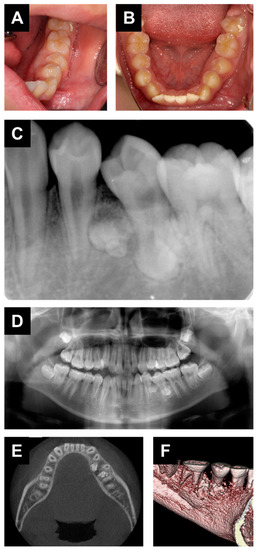

2. Case Report